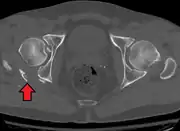

Axial CT image (viewed on bone windows) of a complex comminuted left acetabular fracture involving both anterior and posterior columns.